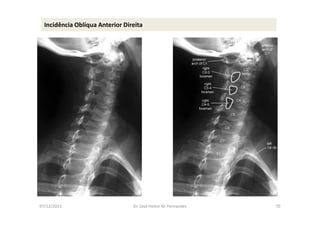

Incidência Oblíqua Anterior Direita

07/12/2015 Dr. José Heitor M. Fernandes 71

• 1- Incidência AP com a boca aberta (para visualizar C1-C2);

• 2- Incidência AP cervical inferior;

• 3- Incidência cervical lateral (perfil);

• 4- Incidências oblíquas direita e esquerda;

• 5- Incidências adicionais: